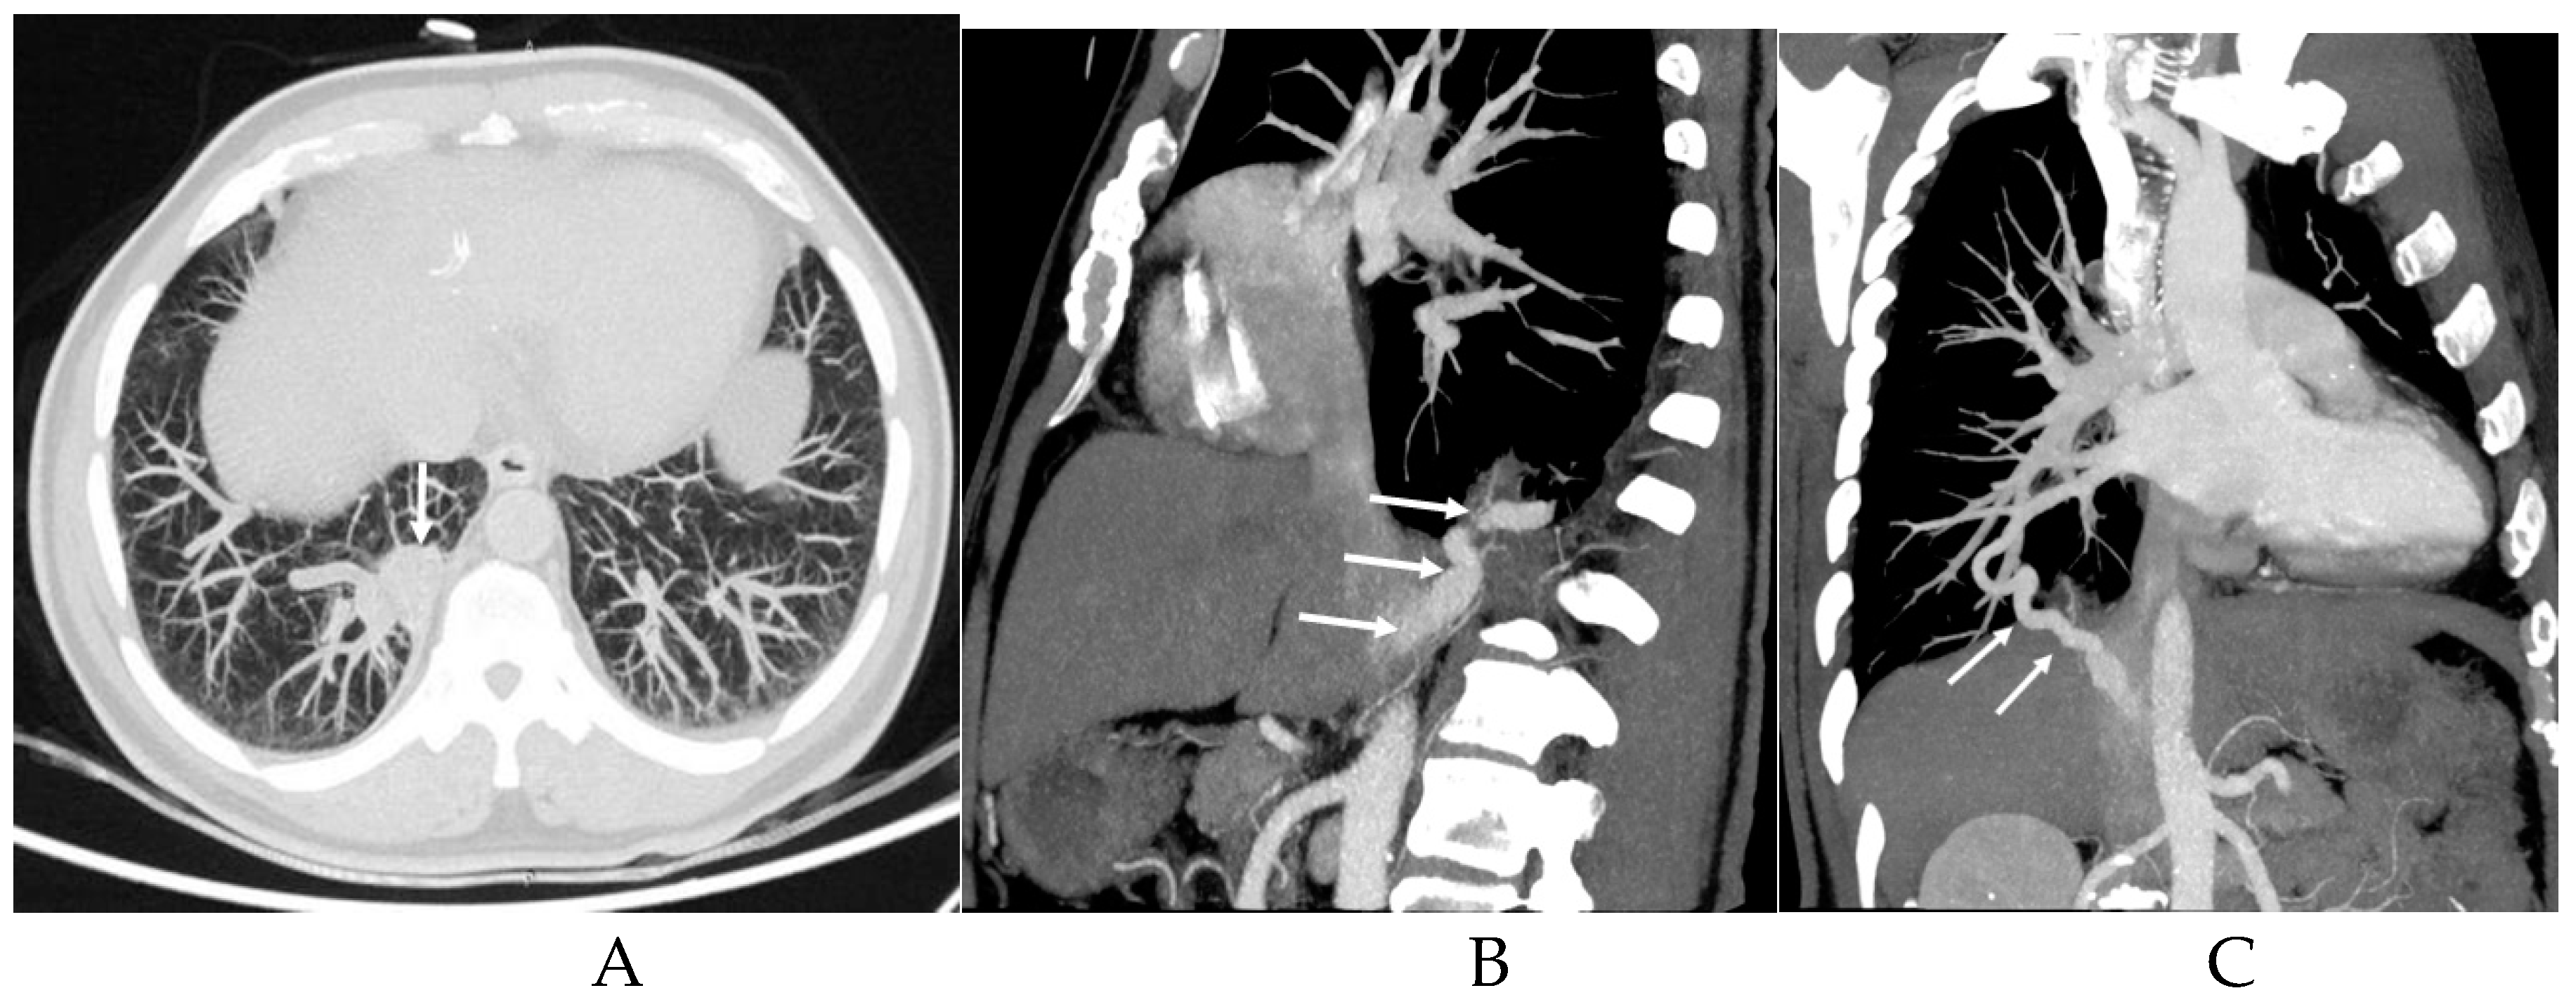

3.2. Imaging appearances of CTPA

| Supplying artery | Aorta A | 1(1.82%) |

| Aorta D | 47(85.45%) | |

| CA | 7(12.73%) | |

| BA | 1(1.82%) | |

| Draining vessels | PV | 49(89.09%) |

| UV | 1(1.82%) | |

| IV | 1(1.82%) | |

| PA | 11(20.00%) | |

| NF | 2(3.64%) |